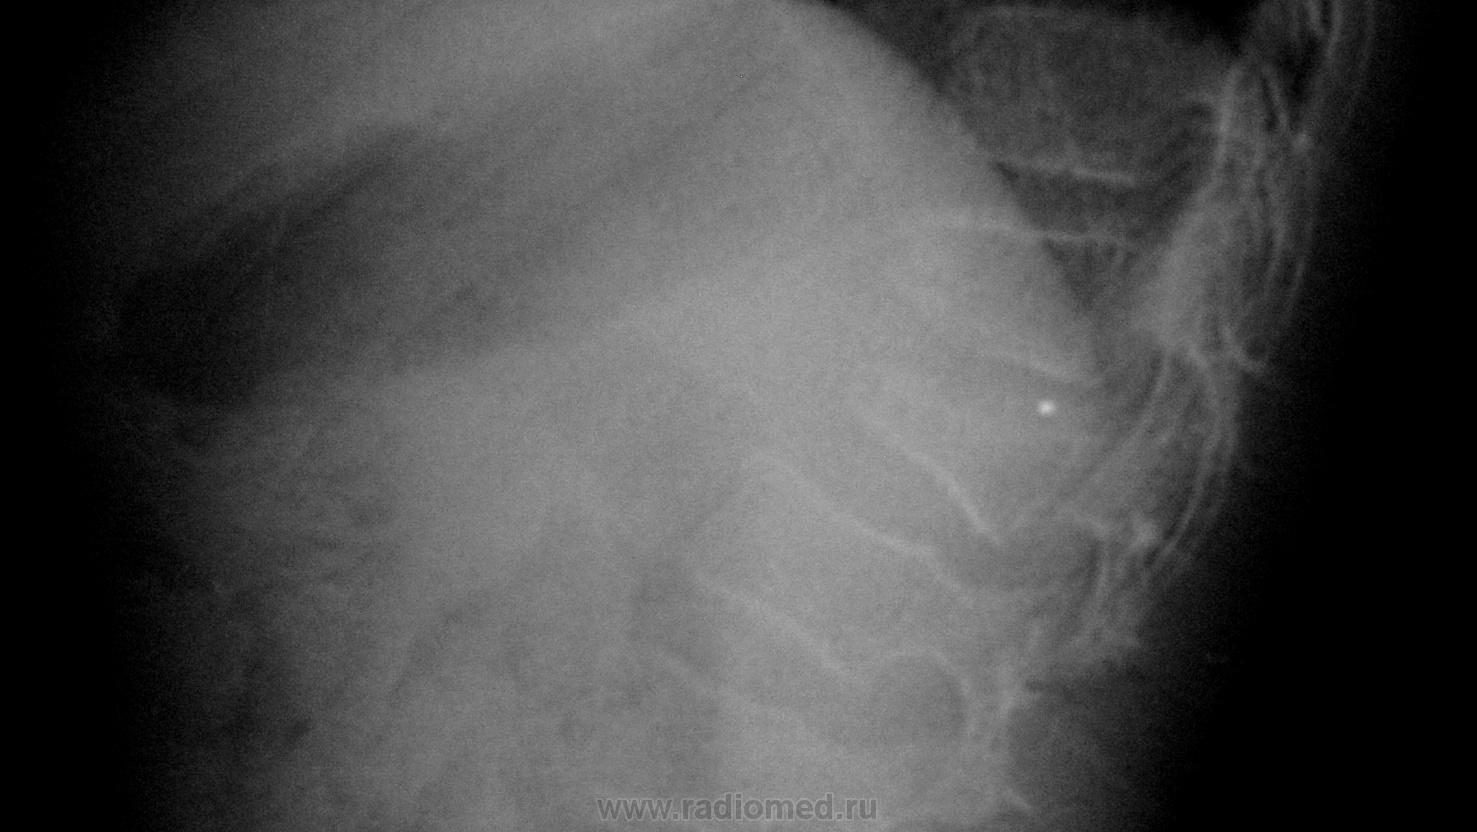

Пол пациента: Женский пол Тип патологии: Травма Область исследования: Скелетно-мышечная система Методы исследования: Rg На прием обратилась девочка 12 лет, в анамнезе падение с высоты 3метров на спину. https://radiomed.ru/sites/default/files/styles/case_slider_image/public/user/8914/kopiya_kompres.perelom_l2.jpg?itok=lWElrwcG ID:12352 Чт, 03/03/2011 - 19:57 #1 DR.RAD Не на сайте Был на сайте: 11 лет 9 месяцев назад Зарегистрирован: 25.03.2009 - 18:22 Публикации: 805 сломано 2 позвонка, а что смущает?))) Чт, 03/03/2011 - 19:59 #2 DR.RAD Не на сайте Был на сайте: 11 лет 9 месяцев назад Зарегистрирован: 25.03.2009 - 18:22 Публикации: 805 хотя нет, по КТ один позвонок да? Чт, 03/03/2011 - 23:49 #3 Петрович Не на сайте Был на сайте: 7 лет 3 месяцев назад Зарегистрирован: 22.03.2009 - 01:13 Публикации: 3908 Всё же 2, но разная степень компрессии. Неоднозначно всё Пт, 04/03/2011 - 04:19 #4 Демчев Валентин... Не на сайте Был на сайте: 7 лет 8 месяцев назад Зарегистрирован: 08.02.2011 - 15:40 Публикации: 445 Ничего не смущает, на фоне этой травмы, сформировался лордосколиоз2 степени. И не вполне ясные перспективы на будущее.Приложения: Пт, 04/03/2011 - 14:43 #5 Nela Не на сайте Был на сайте: 6 лет 1 месяц назад Зарегистрирован: 12.05.2009 - 20:43 Публикации: 1847 Насчет перспектив, это к травматологам. А прямые снимки есть? Пт, 04/03/2011 - 15:28 #6 Евгений1313 Не на сайте Был на сайте: 13 лет 2 недели назад Зарегистрирован: 15.10.2010 - 19:13 Публикации: 808 Кифо -сколиоз.. Пт, 04/03/2011 - 18:02 #7 Демчев Валентин... Не на сайте Был на сайте: 7 лет 8 месяцев назад Зарегистрирован: 08.02.2011 - 15:40 Публикации: 445 Я думаю у нее патологический лордоз.Приложения: Пт, 04/03/2011 - 19:00 #8 Nela Не на сайте Был на сайте: 6 лет 1 месяц назад Зарегистрирован: 12.05.2009 - 20:43 Публикации: 1847 Возможно гиперлордоз компенсирует локальный кифоз Th12-L1. А у Вас какая версия? Сб, 05/03/2011 - 09:47 #9 Vega Не на сайте Был на сайте: 6 дней 12 часов назад Зарегистрирован: 22.01.2009 - 19:16 Публикации: 1087 Nela wrote: Возможно гиперлордоз компенсирует локальный кифоз Th12-L1. Абсолютно правильно. Необходимо решать вопрос об оперативном лечении... Сб, 05/03/2011 - 17:30 #10 Nela Не на сайте Был на сайте: 6 лет 1 месяц назад Зарегистрирован: 12.05.2009 - 20:43 Публикации: 1847 Здравствуйте, Vega! Давно Вас не было слышно.

сломано 2 позвонка, а что смущает?)))

хотя нет, по КТ один позвонок да?

Всё же 2, но разная степень компрессии.

Ничего не смущает, на фоне этой травмы, сформировался лордосколиоз2 степени. И не вполне ясные перспективы на будущее.

Кифо -сколиоз..

Я думаю у нее патологический лордоз.

Возможно гиперлордоз компенсирует локальный кифоз Th12-L1.

Абсолютно правильно.

Необходимо решать вопрос об оперативном лечении...